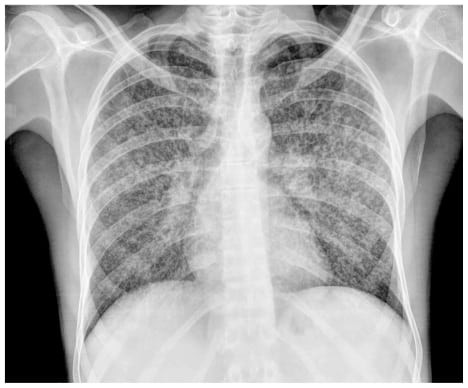

TAG: Tuberkulosis

Ada 35 Artikel yang mempunyai tag "Tuberkulosis"